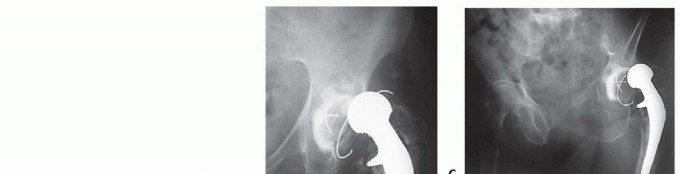

DEFINITION One of the significant challenges in hip revision surgery is the absence of satisfactory proximal …

DEFINITION Hip reimplantation refers to the insertion of another prosthesis after removal of the original, in…